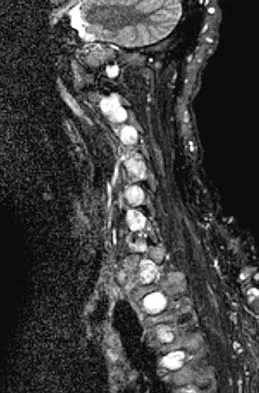

Question 27

A 68-year-old man reports a 1-year history of debilitating neck pain without neurologic symptoms. History reveals a C5-6 anterior diskectomy and bone grafting 10 years ago that provided good relief of arm and neck pain. Radiographs show evidence of fibrous union at C5-6, spondylotic disk narrowing at C4-5 and C6-7, and a fixed 2-mm subluxation at C3-4. Examination reveals cervical stiffness and discomfort at the extremes of movement. His neurologic examination is normal. Treatment should now consist of